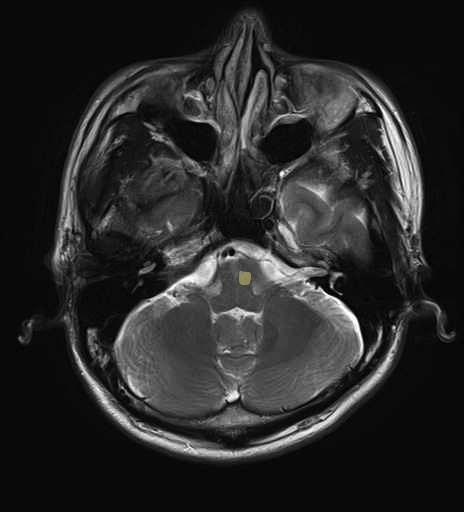

運動系 錐体路系に色を付けました。

■皮質脊髄路(いわゆる錐体路):一次運動野から脊髄遠隔の下位運動ニューロン細胞体まで

■皮質核路:一次運動野から橋及び脊髄神経核まで